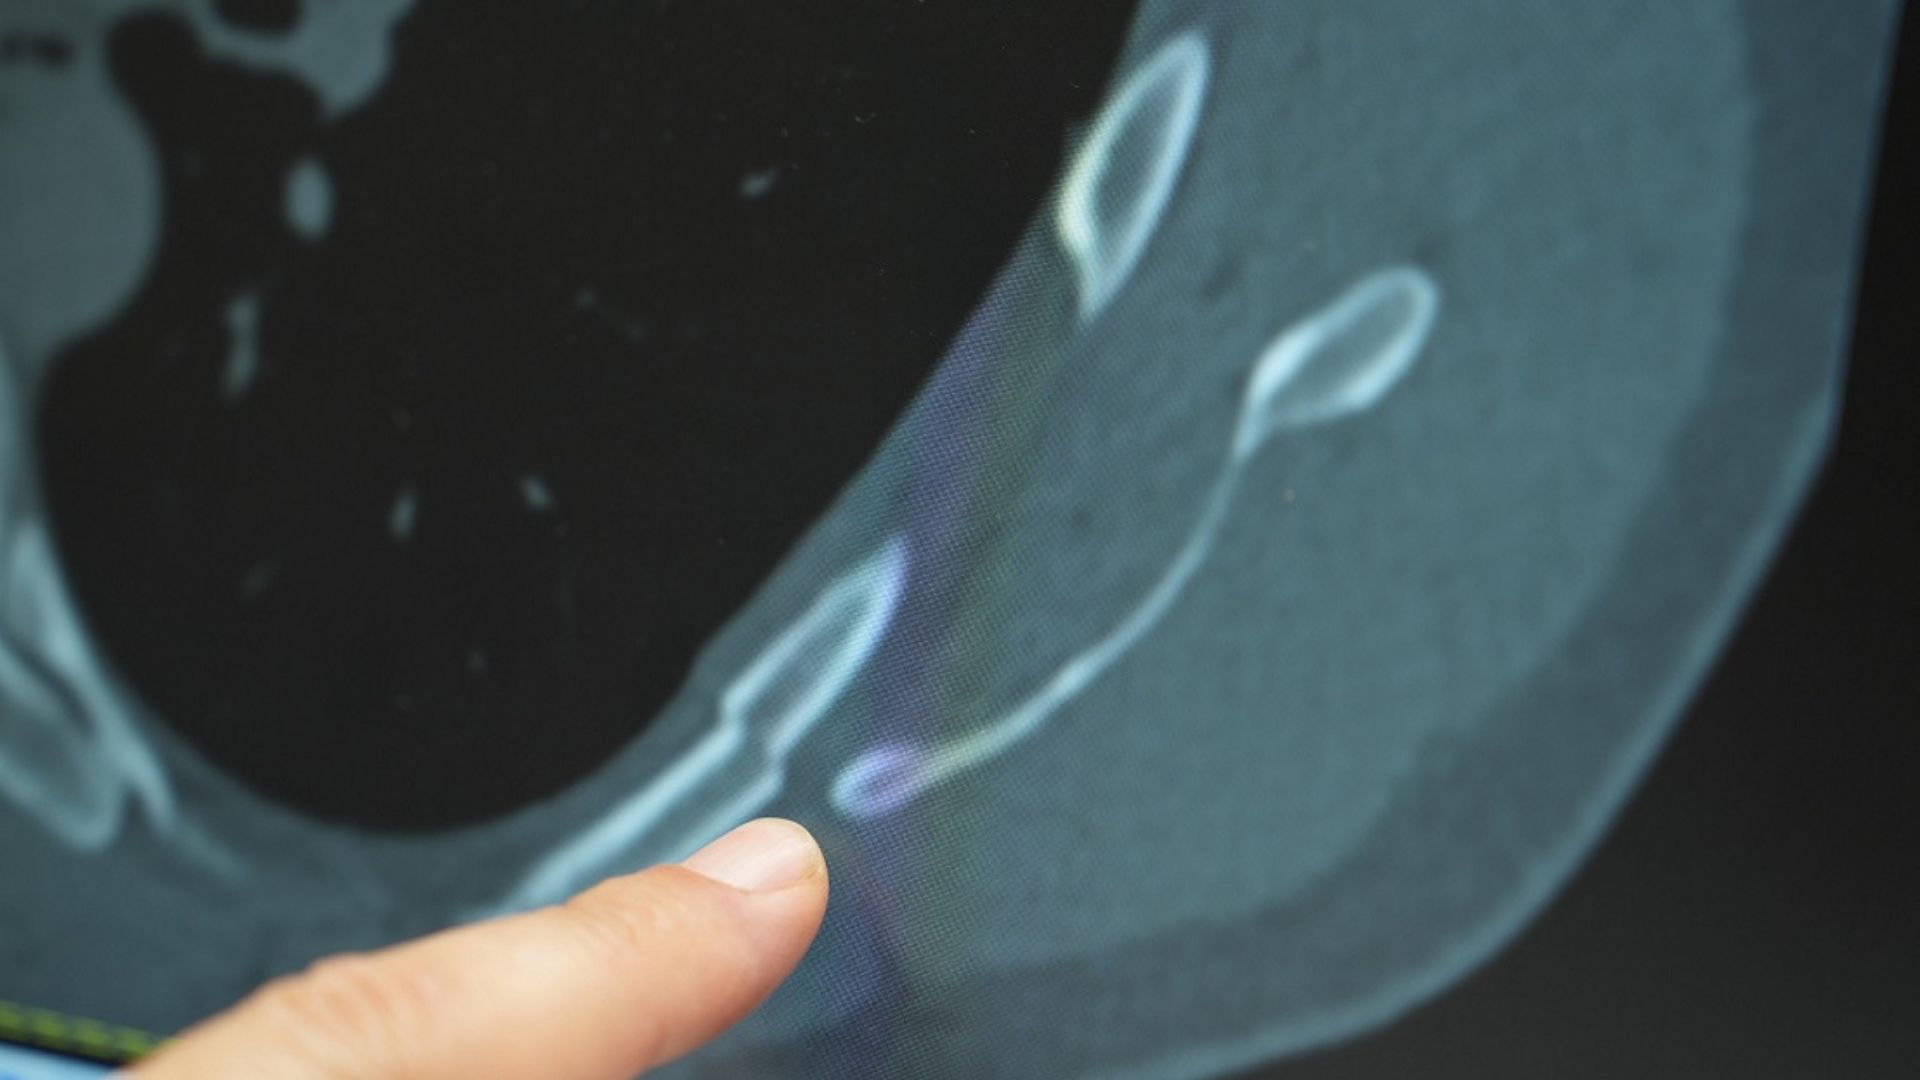

Prof. Dr. Güven Sadi Sunam, gençlerde görülen göğüs ağrılarının çoğunlukla ani öksürük sonrası başladığını ifade ederek, “Hastalar bize göğüs ağrısıyla başvuruyor. Yapılan detaylı incelemelerde kaburga kırıklarını tomografi ile saptıyoruz” dedi.